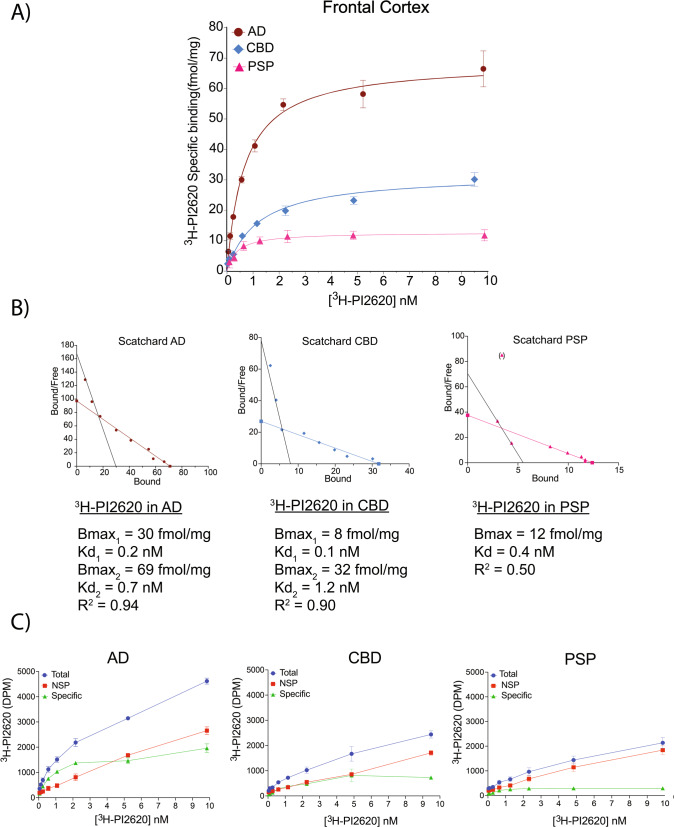

The saturation binding study results for 3H-PI2620 in AD, PSP and CBD FC brain homogenates and the corresponding Scatchard plots are shown in Fig. 1A and Fig. 1B, respectively. For the AD tissue, saturation occurred at a Kd2 of 0.7 nM and Bmax2 of 69 fmol/mg. A second binding site was observed when the Scatchard plot was manually drawn (Kd1 = 0.2 nM; and Bmax1 = 30 fmol/mg). For the CBD tissue, saturation occurred at a Kd2 of 1.2 nM and Bmax2 of 32 fmol/mg. The Scatchard plot revealed a second binding site (Kd1 = 0.1 nM; and Bmax1 = 8.0 fmol/mg). For PSP tissue, the saturation curve displayed one binding site with a Kd of 0.3 nM and Bmax of 12 fmol/mg. The total, NSP and specific binding results for 3H-PI2620 are shown in Fig. 1C. For the AD tissue, total binding increased with increasing 3H-PI2620 concentrations and NSP binding increased linearly, while specific binding increased up to a concentration of 2 nM where it reached a plateau. The total binding for the CBD tissue was similar to that for the PSP tissue, but NSP binding was much higher in PSP tissue than in CBD tissue.

3H-PI2620 saturation studies in AD, CBD and PSP brains

3H-PI2620 saturation binding studies in the FC of CBD brains demonstrated the presence of two binding sites, as in AD brains but only one site in PSP brains. The binding affinities of the binding sites in CBD and PSP brains were almost comparable to those in AD brains (Kd ranging from 0.1 to 1.2 nM). The main difference was in the Bmax (site density) values. The Bmax in CBD brain tissue was 2-fold lower than that in AD brain tissue whereas, in PSP, Bmax was almost 6-fold lower than in AD brain tissue. Thus, Bmax was 2.6-fold higher in CBD than in PSP brain tissue. These observations were confirmed by comparing the specific and NSP binding of 3H-PI2620 in these cases. In AD brain tissue, the specific binding was 2.5-fold and 6.5-fold higher than in CBD and PSP brain tissues, respectively.

CBD brains commonly present with high tau levels in the glial cells and neurons of the FC as well as in the basal ganglia and brainstem. However, typical PSP brains primarily present with neurofibrillary tangles in the neurons of the basal ganglia, diencephalon and brainstem [ref. 56], which could explain the lower numbers of 3H-PI2620 binding sites in our saturation studies in the FC of PSP brains. FC was chosen for saturation studies since it was affected in all three pathologies albeit differently. Nevertheless, although the number/density of binding sites might vary by brain region, 3H-PI2620 bound to tissue from the three pathologies with similar high affinity, suggesting the presence of either specific or completely different tau-binding sites (with the same affinity) in these diseases.